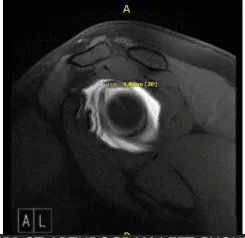

Tras una semana, el paciente regresó con resultados de la resonancia magnética y mostró que la columna cervical mostró un resultado significativo de enderezamiento de la lordosis cervical normal, compatible con un elemento de espasmo muscular, y la resonancia magnética mostró desgarro del labrum glenoides superior que se extendía hacia el ancla, la cabeza larga y el tendón del bíceps.

Artrograma MRI-3T en hombro izquierdo